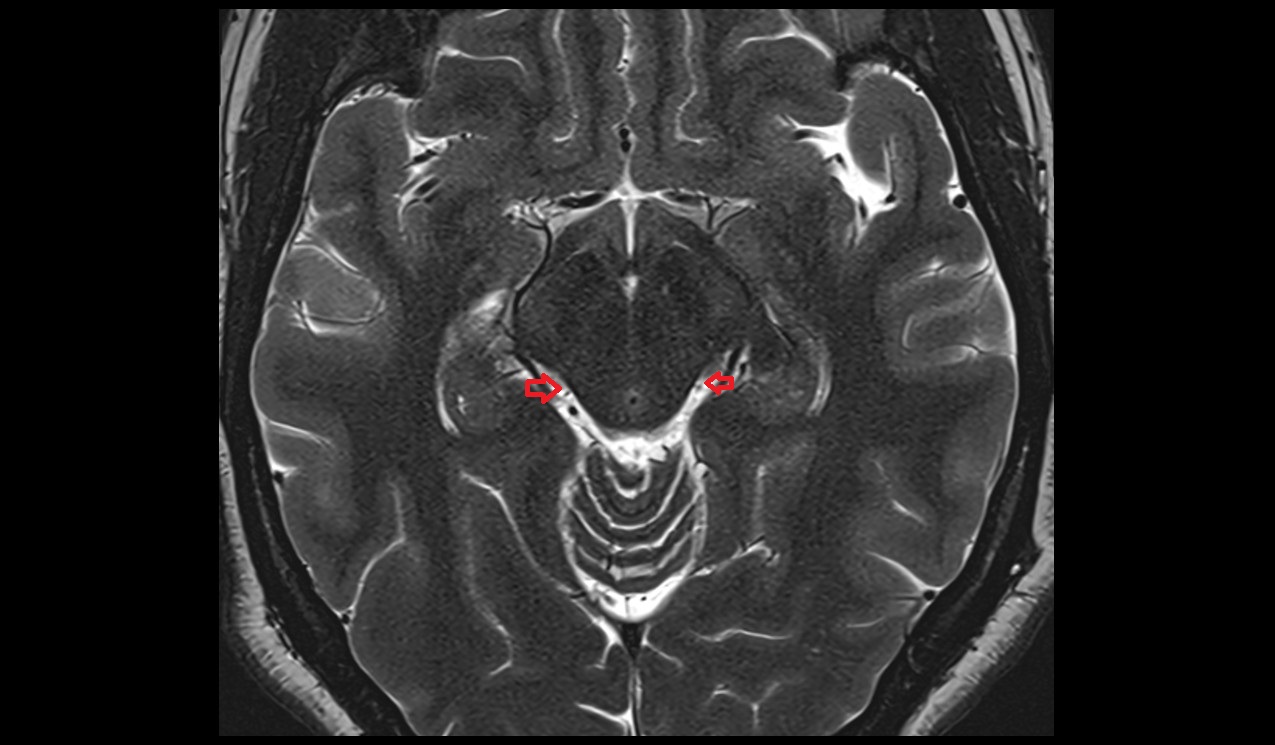

- Lateral aperture of fourth ventricle (foramen of Luschka)

- Lateral aperture of the fourth ventricle

- Lateral recess fourth ventricle

- Cerebellopontine cistern

- Flocculus